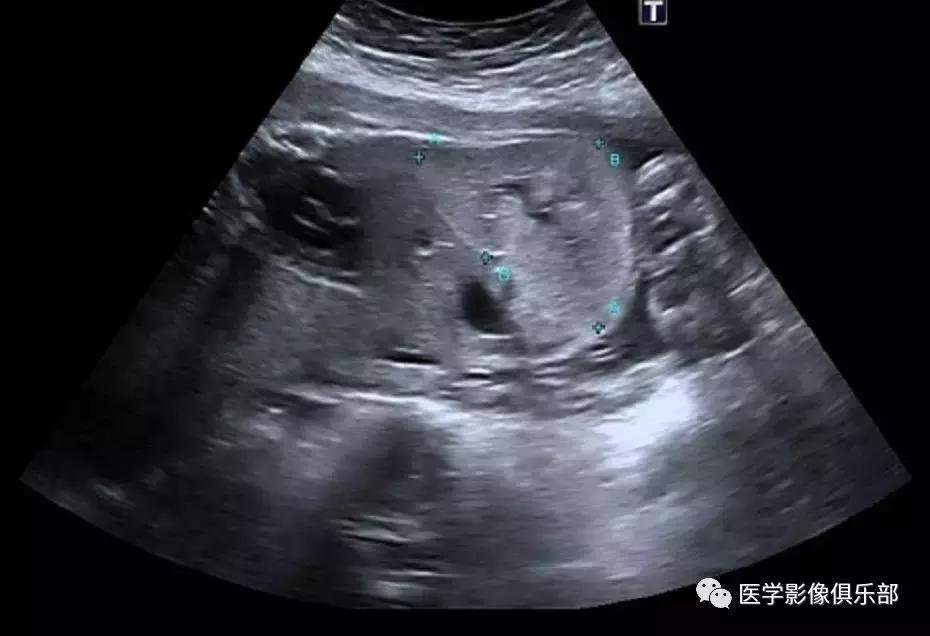

[典型病例二]:45岁,女性患者,腹部不适。家族史是动脉瘤性蛛网膜下腔出血和肾损害。

CTMPR冠状位重建显示双侧肾脏体积明显增大,肾脏皮质及髓质分界不清,弥漫大小不等的囊肿,边界光滑锐利,肝脏实质内亦可见多发大小不等的囊肿。